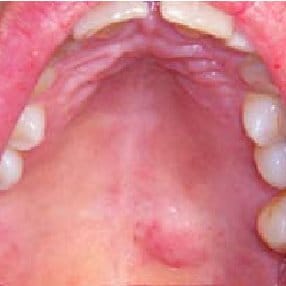

- Obstrucción o tumor benigno de una glándula salival o bien producido en la bóveda palatina.

Un absceso (acumulación de pus por sobreinfeccion bacteriana, hongos). Que con el tiempo se secó y de esa forma quedó enquistado.